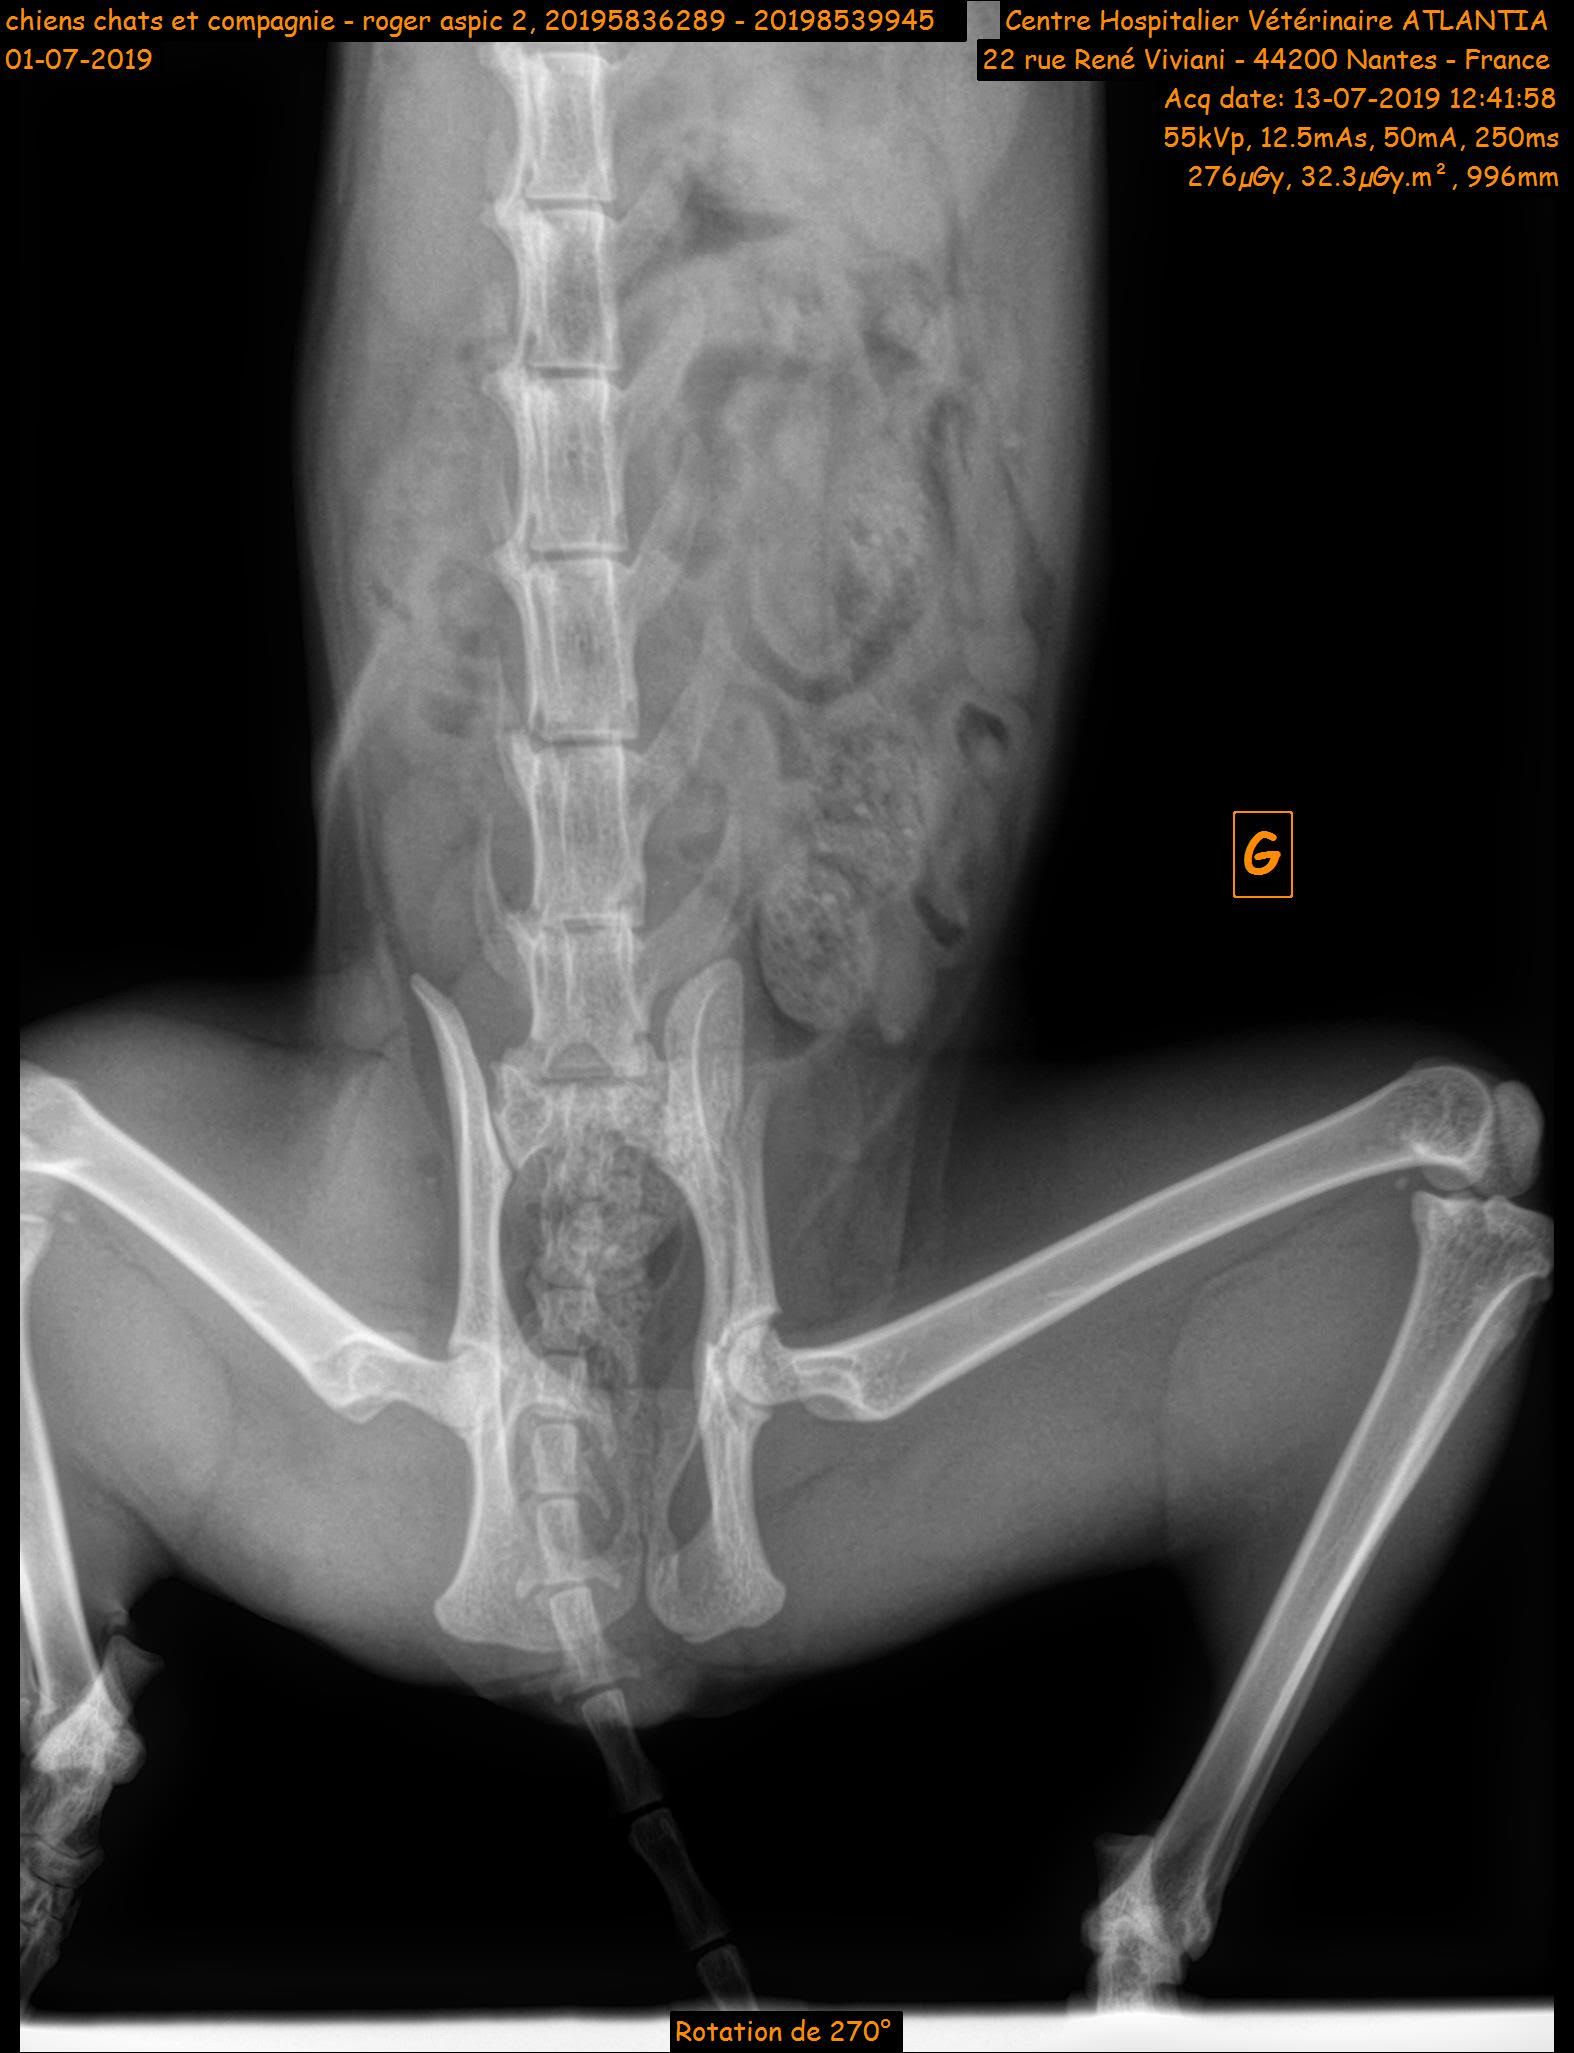

NOUGAT a été opéré de sa fracture fémorale. Les fractures du bassin quant à elles se cicatriseront toutes seules.

A sa présentation au vétérinaire, NOUGAT souffrait de nombreuses plaies d’abrasion, d’une double disjonction sacro-iliaque, d’une fracture pubienne et d’une fracture de Salter Harris de type I de la tête du fémur.

Les disjonctions sacro-iliaques droite et gauche se consolideront par elle-même avec l’observation d’une période de repos. En revanche, une intervention chirurgicale a été nécessaire afin de retirer la tête du fémur. Cela ne posera pas de problème pour sa vie future. Des soins de plaies ont également été faits tous les jours.